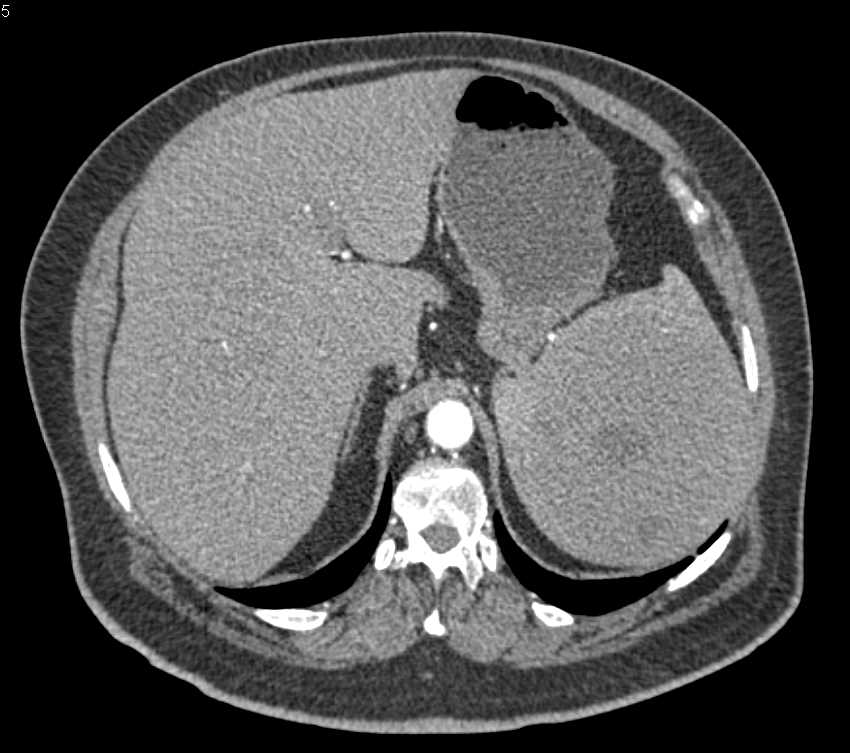

Splenic Hamartoma